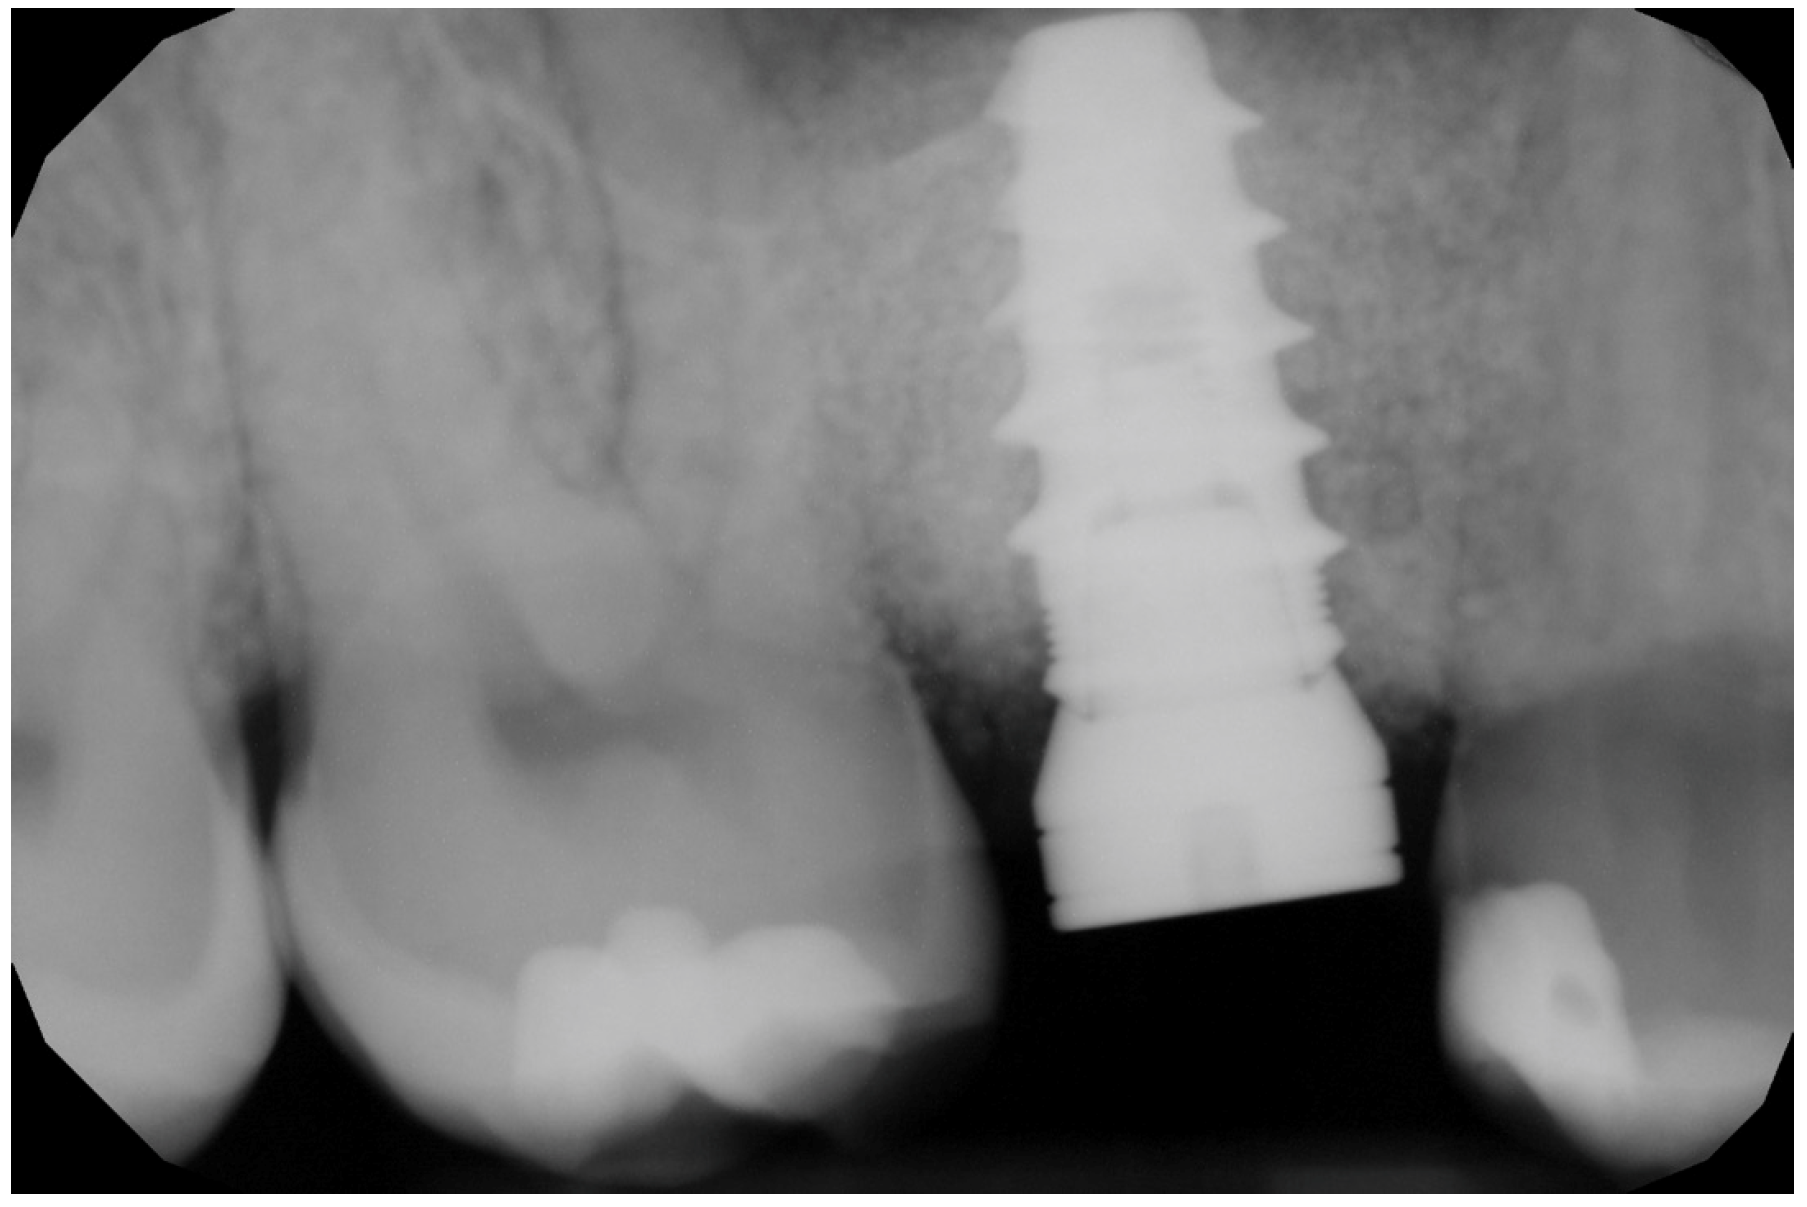

2.6. Case Presentation. Nano-HA Applied to Socket Preservation Procedures

3. Results